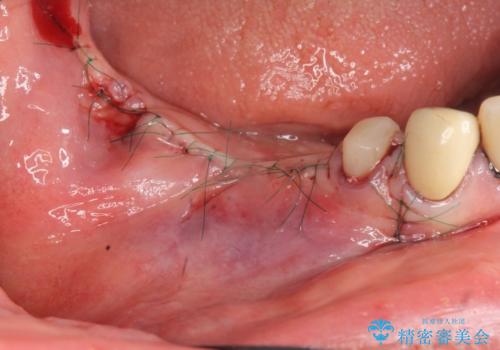

また骨の問題だけでなく、完成後に歯ブラシがしやすいよう歯ぐきの移植も行いよりインプラント周囲の環境が安定するよう環境を整える治療計画を立てます。

また、機能したインプラントを長持ちさせるために清掃性を高めるために硬い歯ぐきを移植することは非常に有効です。